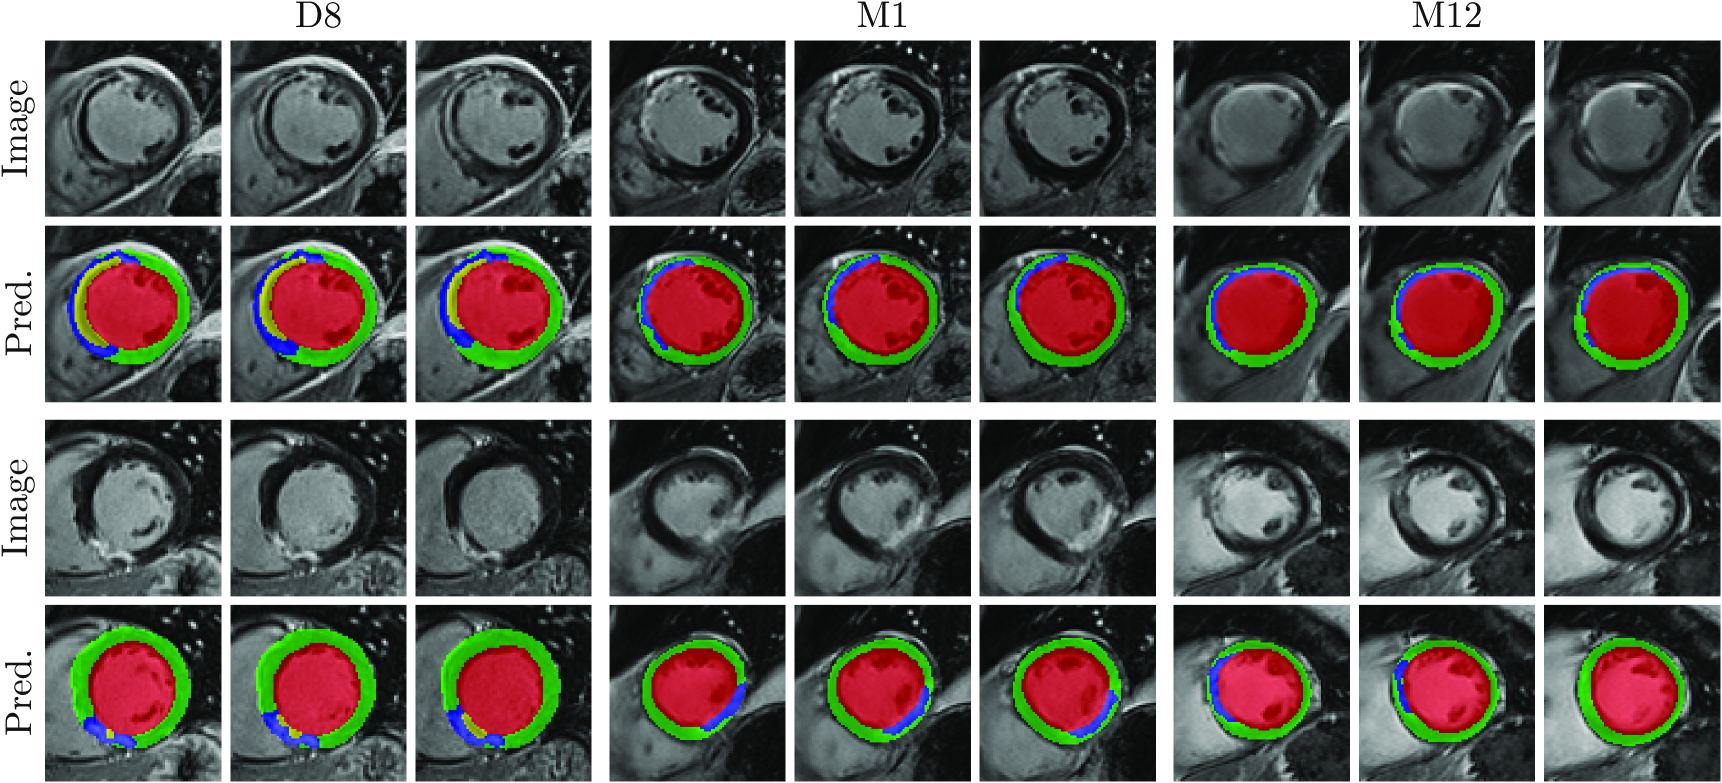

Figure 5: Qualitative results of CaRe-CNN on the validation set. Columns refer to three consecutive slices of LGE MR scans of patients after MI for the three subgroups: D8 (col. 1-3), M1 (col. 4-6) and M12 (7-9). Rows refer to scans of two separate patients and show the image (rows 1, 4), ground truth (rows 2, 5) and prediction of CaRe-CNN (rows 3, 6).

The qualitative evaluation of our CaRe-CNN is performed by visually inspecting the predictions. As ground truth segmentations for the test set data are hidden, we also present qualitative results of CaRe-CNN trained on 2/3232/32 / 3 and validated on 1/3131/31 / 3 of the actual training data for the MYOSAIQ challenge in Fig. 5 to allow a comparison of our predictions to the ground truth. Additionally, we provide qualitative results of our final method submitted to the challenge on the test set in Fig. 6, however, without publicly available ground truth segmentations, the predictions are only compared to the respective input images. Both figures show three consecutive slices of two MR scans of patients after acute MI per subgroup (D8, M1, M12).

The qualitative results on the validation set in Fig. 5 confirm that most label predictions are very close to the ground truth. On closer inspection, however, some differences can be spotted. For example, one of the two MVO regions is predicted in one additional consecutive slice in contrast to the ground truth (D8, top), while the MIT label is overpredicted close to the apex (M1, bottom). Also, an MVO label prediction for a patient without MVO is visible (D8, bottom). Nevertheless, many regions are predicted correctly, most notably even for data where the wall is in parts only two to three voxels thick (M12, bottom). On the test set in Fig. 5, qualitative results can only be compared to the LGE MR image. Overall, the label predictions appear to be realistic which is supported by our quantitative evaluation, however, further confirmation needs to be performed by an expert.